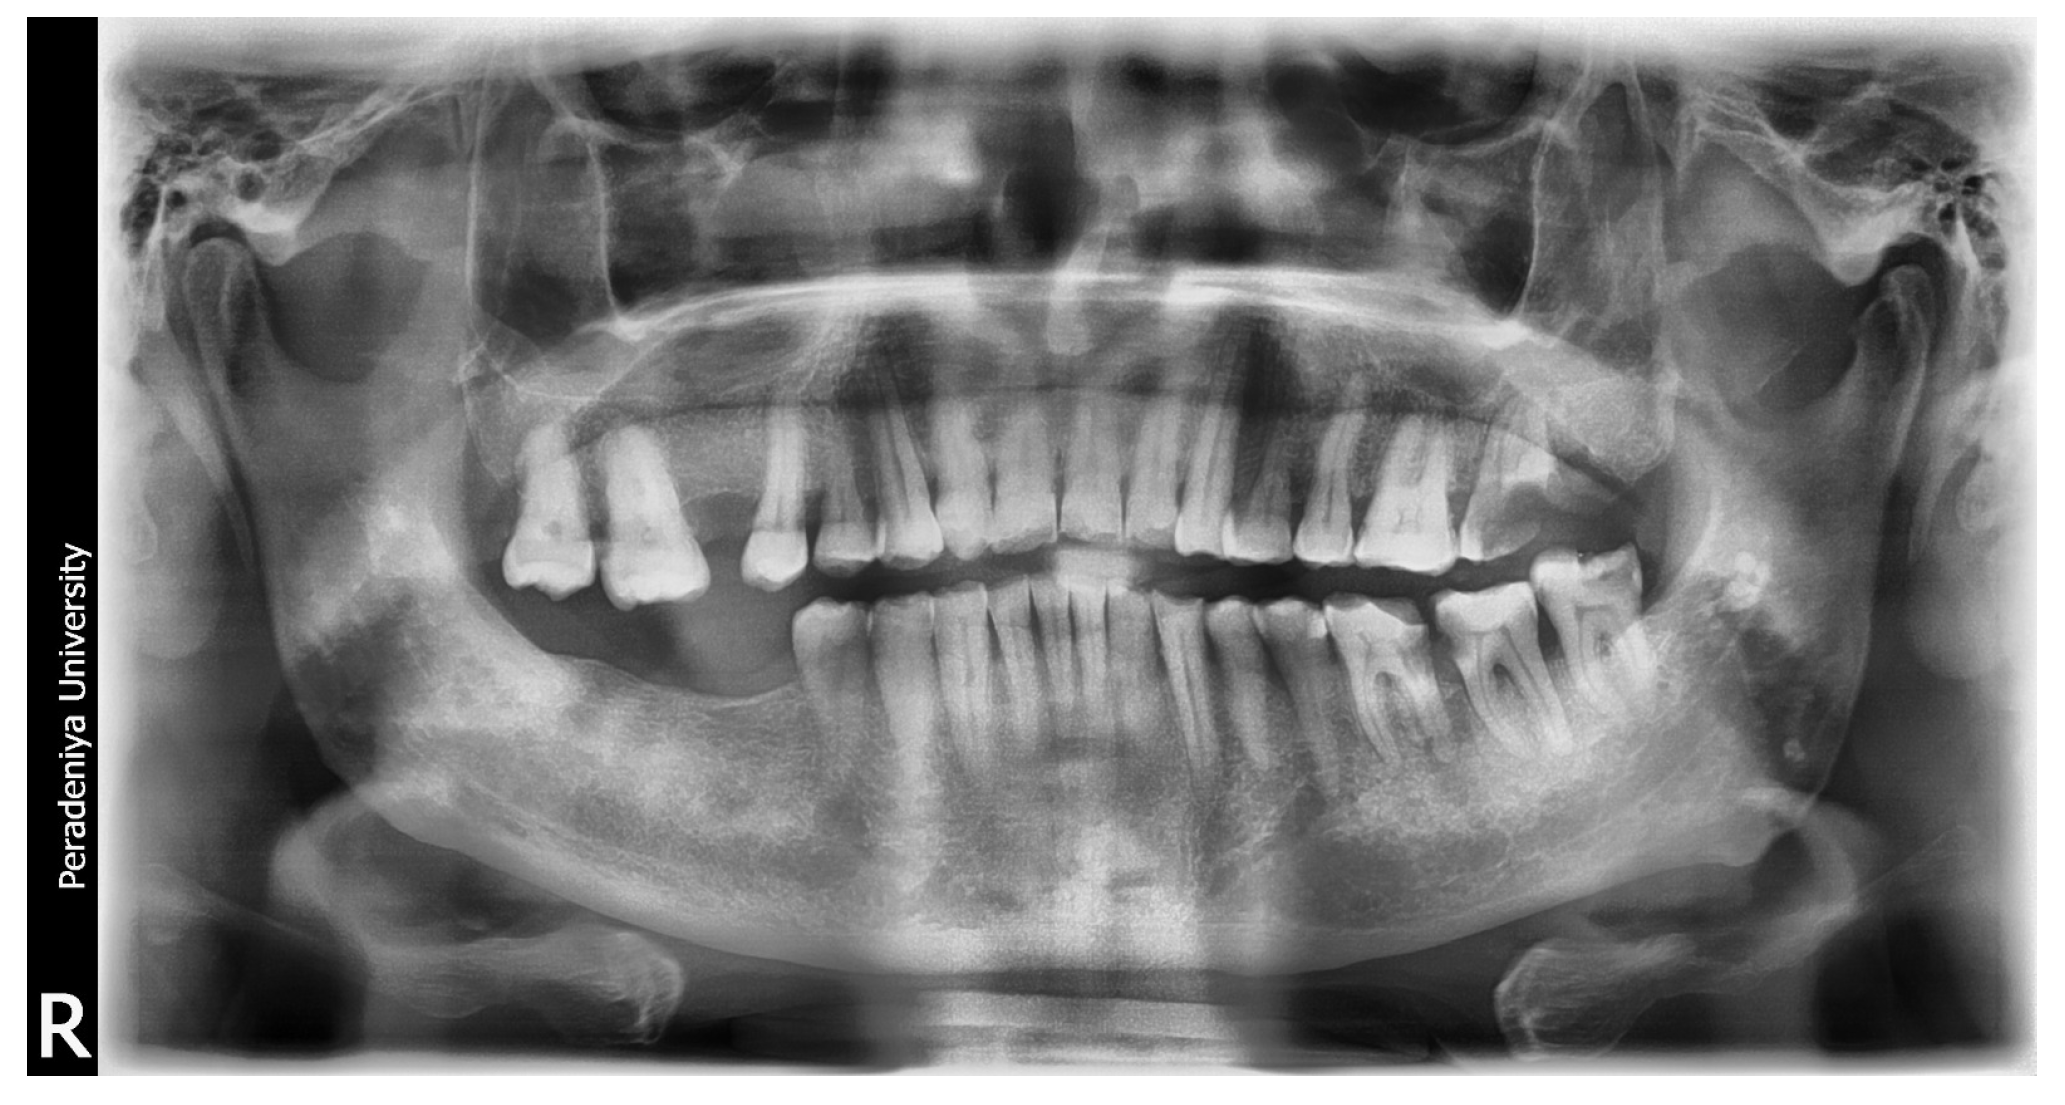

Sample DPT image 01.

Figure A3.

Figure A4.

AI-generated report for DPT image 01. This report received a high subjective score for identifying oral conditions in DPT Image 01.